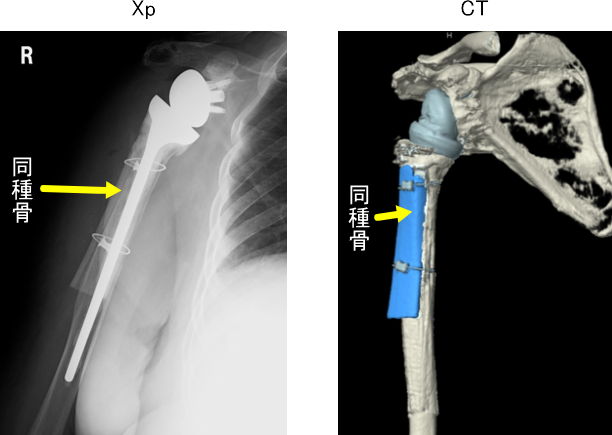

そこで同種脛骨というものを使用します。

この方には、脛骨の同種骨を使用しました

同種骨をワイヤーで上腕骨に固定することで骨の割れ目がふさがるようにいたします。

術直後画像

同種骨は3年たっても上腕骨に固定され、ステムは上腕骨にしっかり固定されています